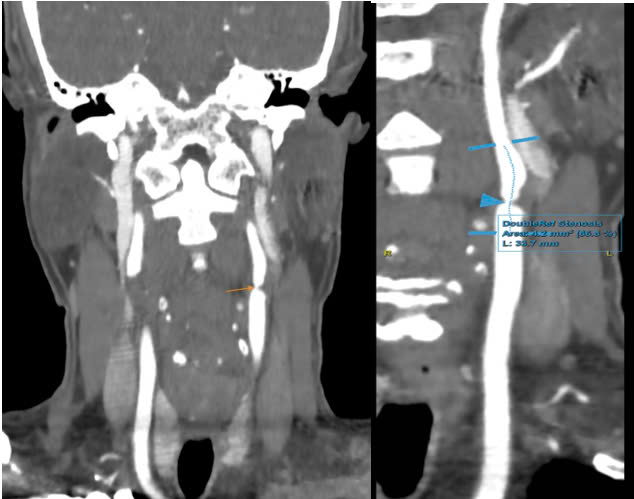

Chưa dừng lại ở đó, hình ảnh MSCT (chụp cắt lớp điện toán đa lát cắt) mạch cảnh xác định mảng xơ vữa mềm gây hẹp tới 86% đoạn gốc động mạch cảnh trong trái, 70% tại vị trí hành cảnh trái, 50% hành cảnh phải và 50% đoạn gốc động mạch cảnh trong phải.

Để đánh giá toàn diện, bệnh nhân được chỉ định thực hiện các xét nghiệm và kỹ thuật chẩn đoán hình ảnh. Kết quả cho thấy chỉ số cholesterol máu tăng cao, đặc biệt là LDL-C (mỡ xấu). Siêu âm mạch cảnh phát hiện mảng xơ vữa kích thước 18x5mm ở xoang cảnh phải gây hẹp 75%, và mảng xơ vữa 15x5mm ở xoang cảnh trái gây hẹp 76%.